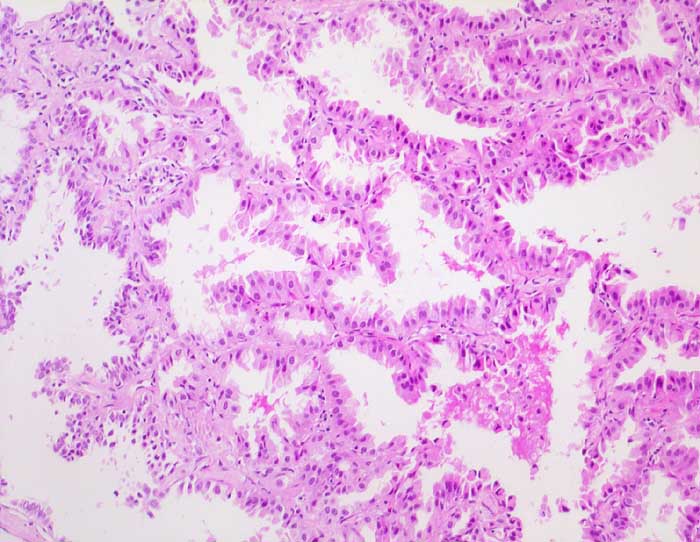

PathoPic – image database / PathoPic ID 6576 - Nicht muzinöses Bronchioloalveoläres Karzinom

Nicht muzinöses Bronchioloalveoläres Karzinom

Die Alveolarsepten werden von hochprismatischen Zellen mit reichlich eosinophilem Zytoplasma ausgekleidet. Das Alveolargerüst ist erhalten und nicht wesentlich verdickt.

Histologie

100